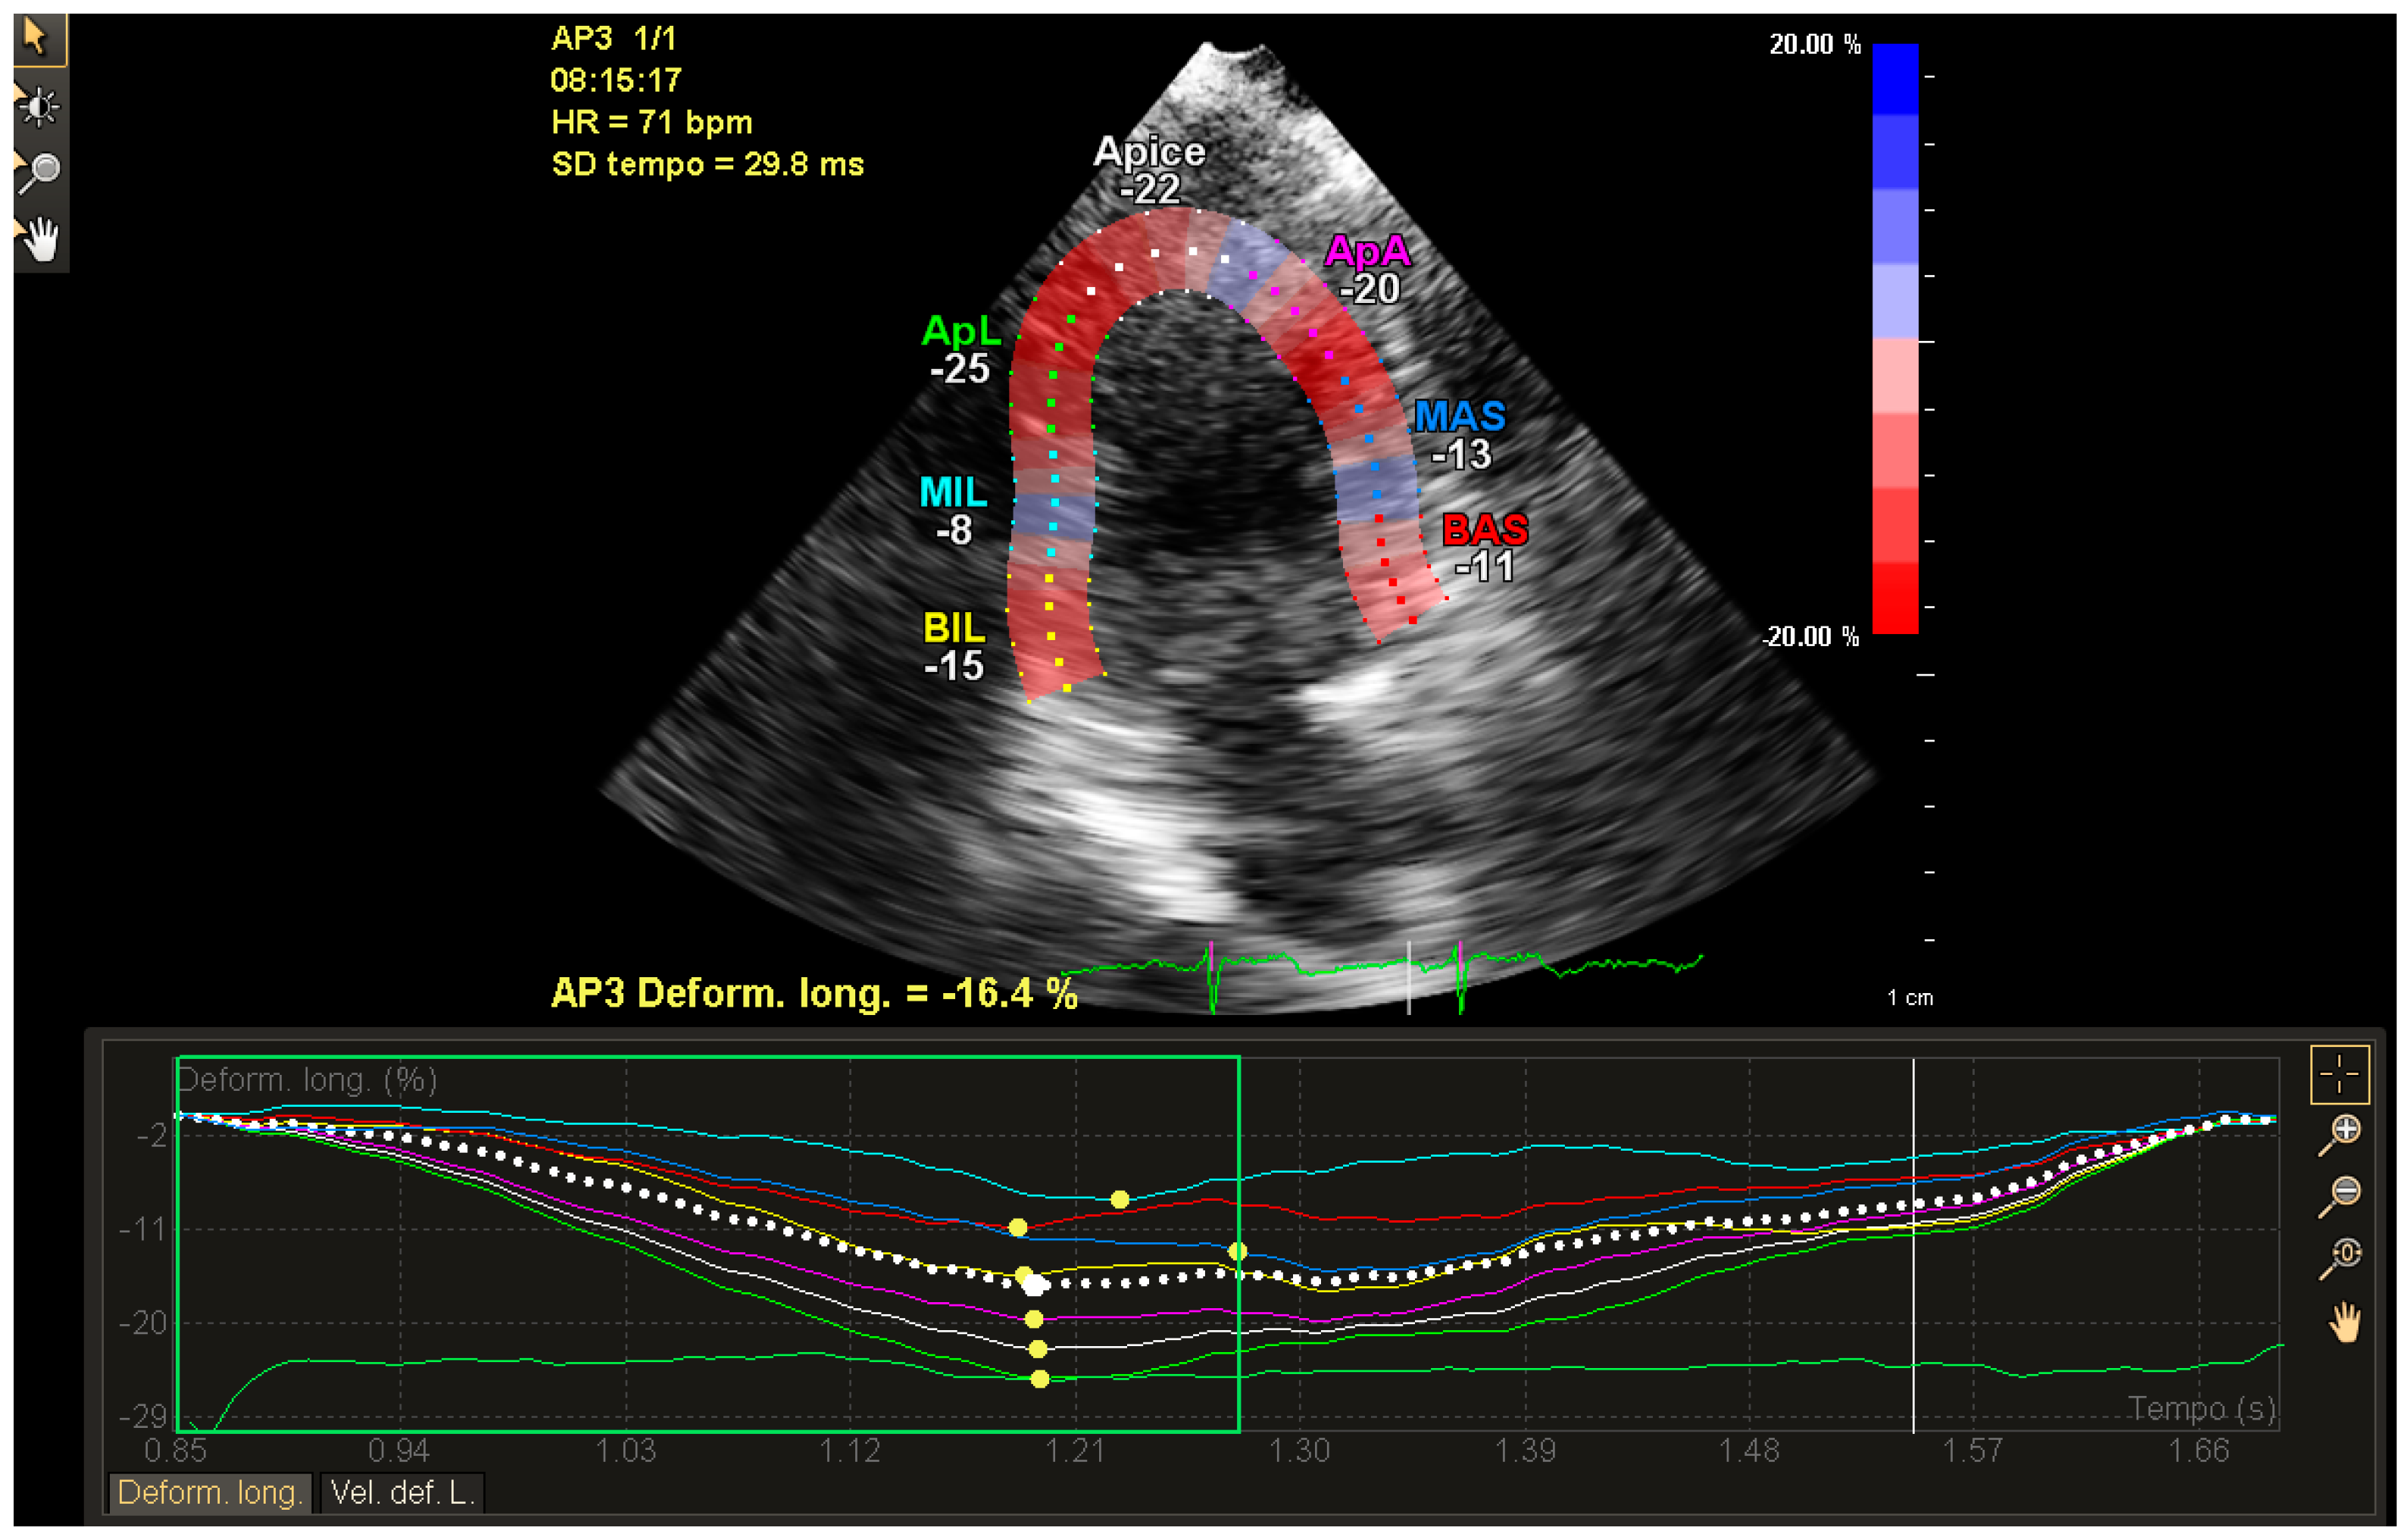

Figure 3.

GLS of LV in breast cancer patient from obtained from a three-chamber view. The post processing analysis has been performed by Q-station, after 5X-1Strain software image acquisition and included in the iE33 Philips echocardiography. The quality of the image is lower than that obtained in the same patient. This is one of the limits of the application The GLS values are in agreement with the values obtained in the other image analysis. In addition, the image shows a delay of strain peak values obtained potentially in accordance with the PSP (Post Systolic Peak) found in the four-chamber view.

In one case, it is particularly important to underline the potential limits due to the image acquisition, to which one is often blinded by the chest conformations. The quality of the image in Figure 3 is lower compared to the other image obtained in the same patient and with the same software. This is one of the potential limits of the clinical applications of this method; however, normally this can be overcome by multiple image acquisition for each patient.